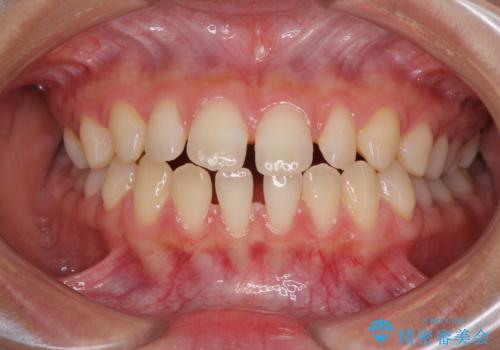

隙間だらけの歯列 インビザラインで改善

- 前歯の上下スペースと前歯の隙間を気にして来院された患者様です。

飲み込みや話をするときに舌を突出させる癖が強くあり、それが原因でスペースが空いていました。

舌癖を改善するためのトレーニングを行いながら、インビザラインにより上下の前歯の隙間を閉じていくこととしました。